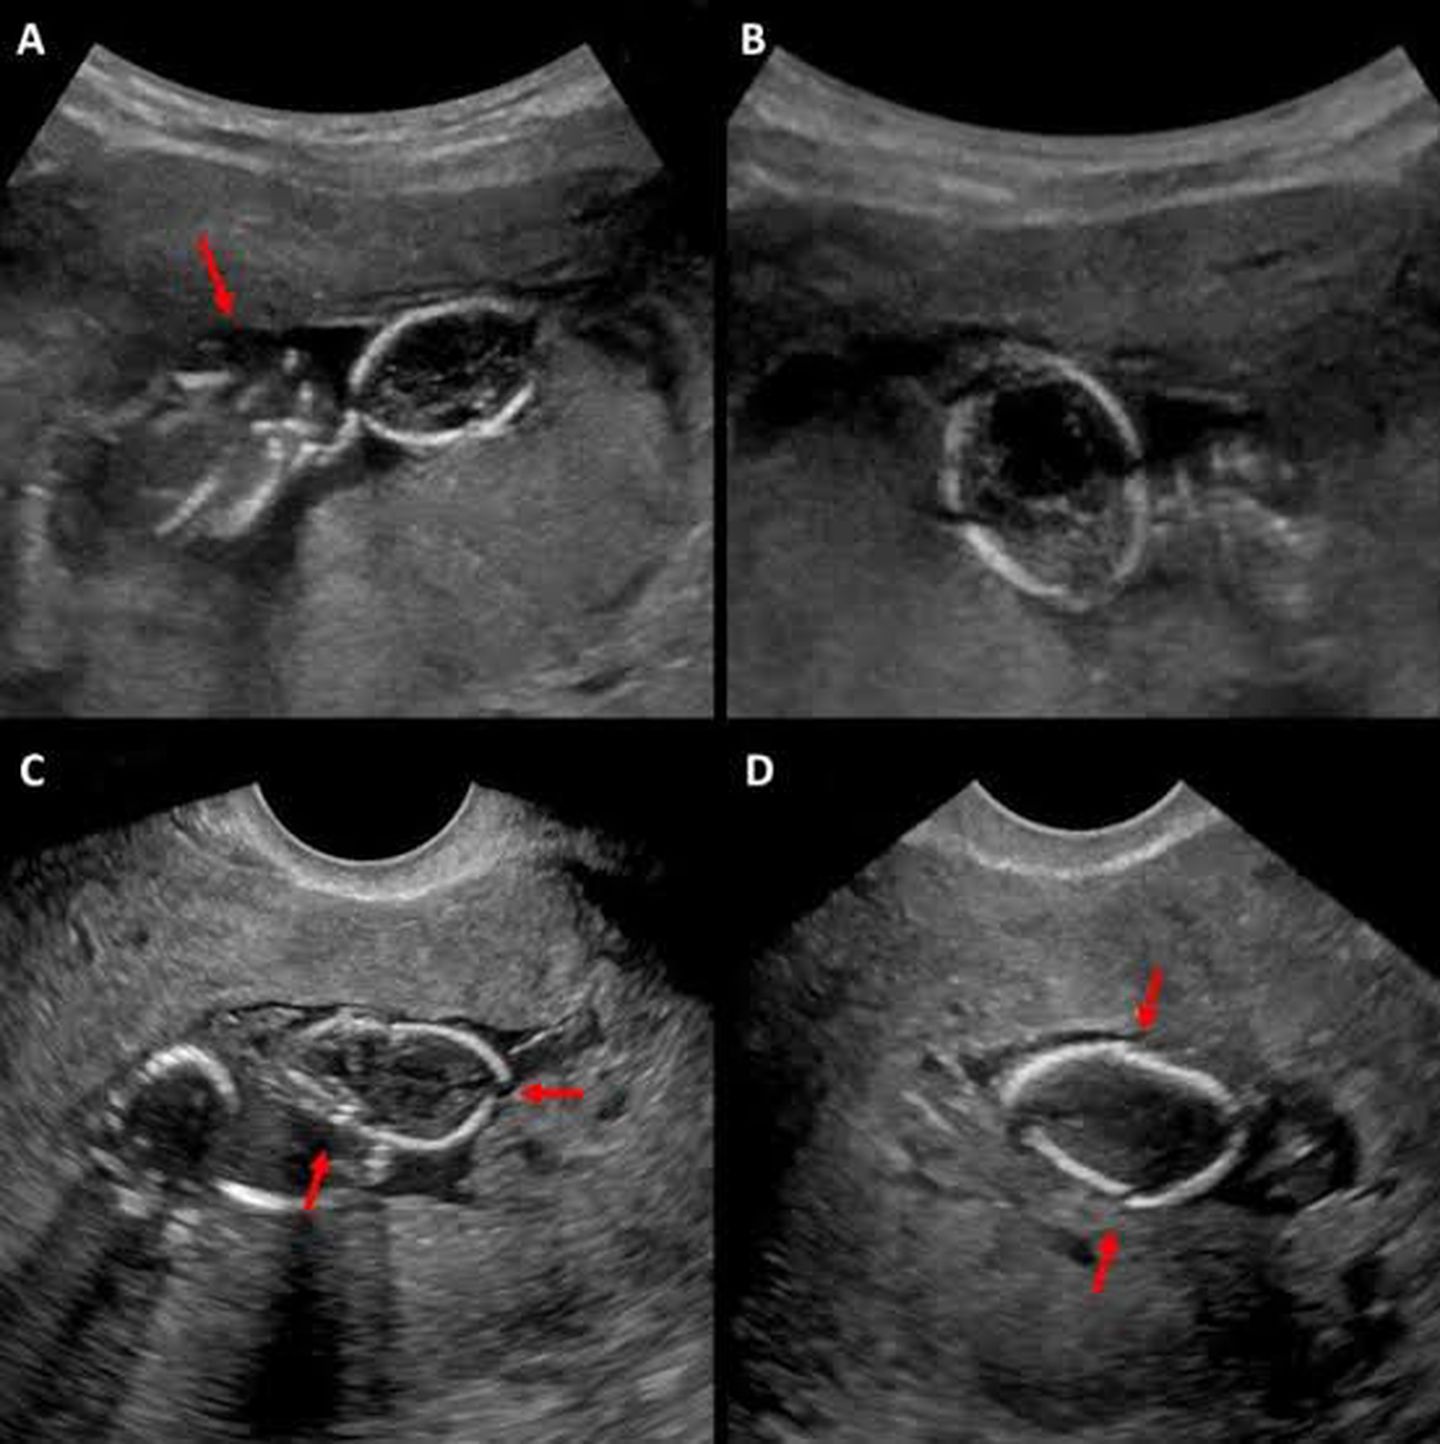

Spalding Sign is a radiological finding in which there is overlapping of the bones of fetal skull. This sign is a diagnostic sign of Intrauterine fetal Death. Other signs of IUD are: - Robert's Sign : A gas shadow found over the fetal heart. - Maceration: Destruction of fetal anatomy with widespread edema. - Helix Sign: Gas present in the Umbilical arteries - Ball Sign: vertebral Spine is Hyperextended Image: Springer Link.